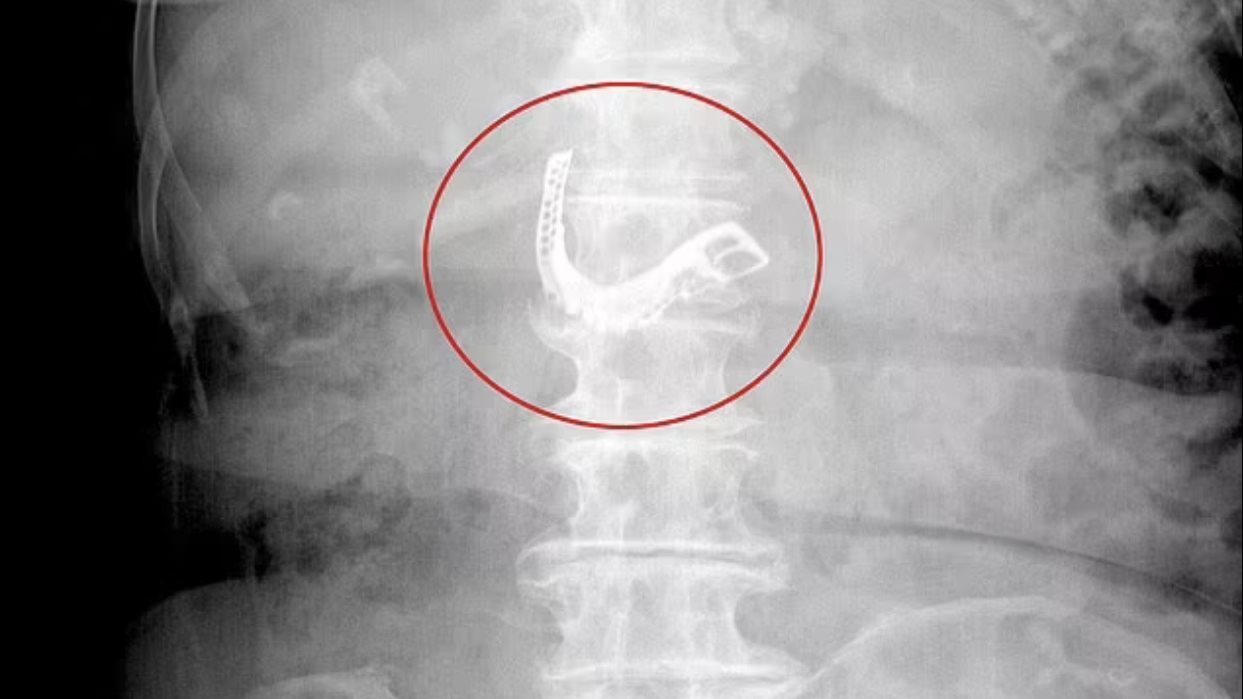

وخلال حديثه أوضح "شادوك" إنه كان مصابًا بـ سرطان الأمعاء على مدار سنوات، ولكن أثناء ضياعه في المحيط واعتماده على نظام غذائي وهو الأسماك النيئة كان اه الفضل في أن يشفى من السرطان.